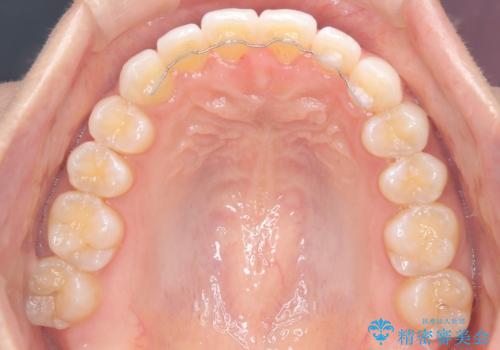

前歯の叢生を非抜歯で改善|インビザライン+IPR・遠心移動・FIX保定

- 前歯部のガタガタ(叢生)を非抜歯で改善するため、インビザラインによるマウスピース矯正を計画しました。抜歯は行わず、歯間をわずかに削るIPR(ディスキング)と奥歯を後方に移動させる遠心移動を併用して、歯を並べるスペースを確保します。歯列が整った後は、FIXリテーナー(固定式保定装置)で後戻りを防止し、安定した歯並びを維持します。

歯を抜きたくないというご希望に応え、インビザラインを用いて非抜歯で歯列を整えました。前歯に必要なスペースを確保するため、歯間をわずかに削るIPRと奥歯を後方に移動する遠心移動を組み合わせました。これにより自然で美しい歯並びを実現。治療終了後は、歯の裏側に目立たないFIXリテーナーを装着し、歯列の後戻りを効果的に防ぎました。患者様は治療中も審美的にストレスなく過ごされ、満足度の高い結果を得られました。